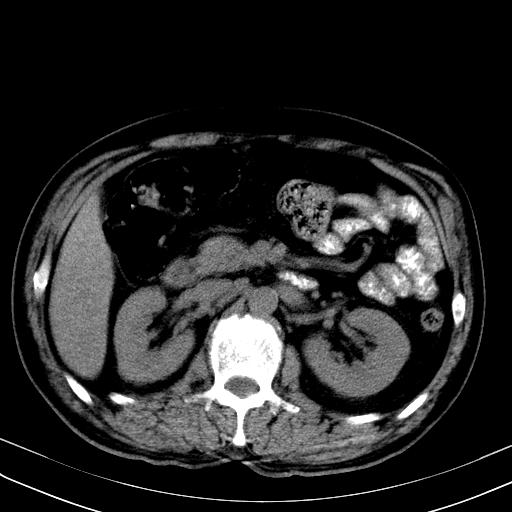

先行ct平扫,纵膈内多发软组织影,ct值约为36hu,以下为增强扫描和腹部平扫。

经典?纵膈多发肿大淋巴结。腹膜后未见异常。

还见胃窦壁增厚!转移亦有可能!

多发肿大淋巴结影,肝内改变需结合强化观察

多发肿大淋巴结影,肝内改变需结合强化观察。